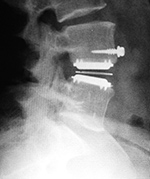

| Metal-on-polyethylene total disk replacement at L4-5 |

47 year-old man |